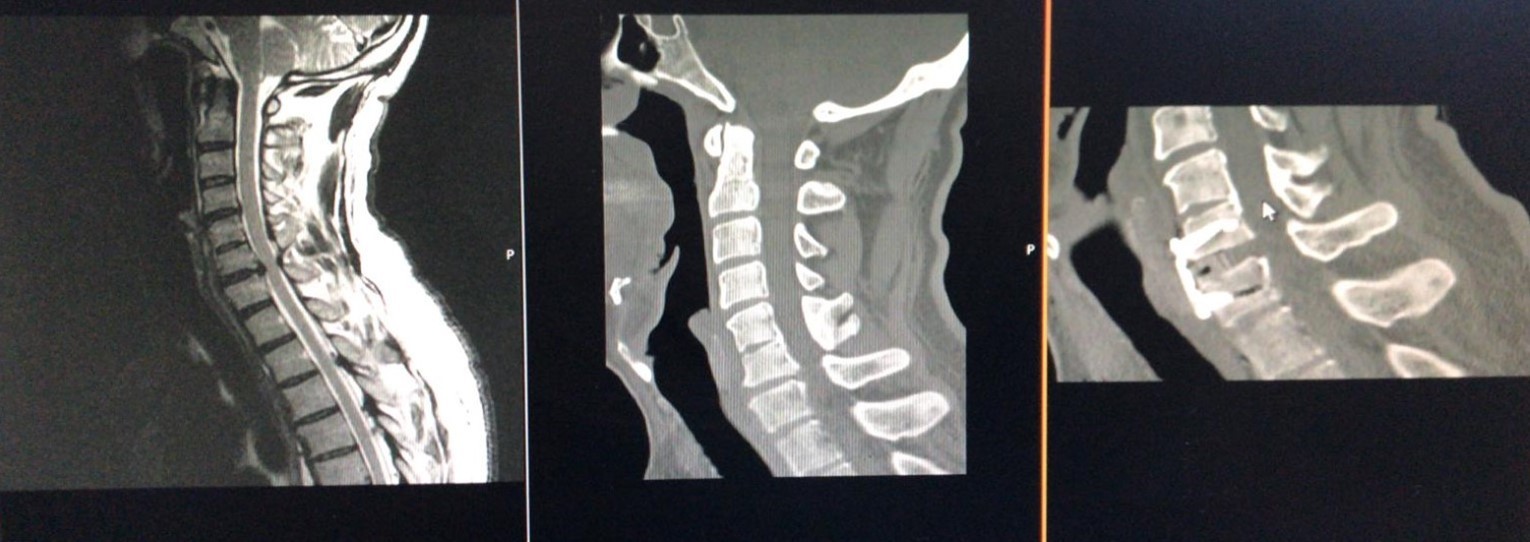

The operative technique was selected concerning our novel “Yilmaz-Yucesoy Classification System” (Table 3). Accordingly, 1 patient (4.54 %) had non-surgical treatment (Yilmaz-Yucesoy Grade 1), 6 patients (27.27 %) received anterior cervical arthroplasty (Yilmaz-Yucesoy Grade 2) (Figure 1), 7 cases (31.81 %) received anterior cervical discectomy or corpectomy and fusion with cervical cage and plate (Yilmaz-Yucesoy Grade 3) (Figure 2). These latter patients did not have cervical spinal instability but had spinal stenosis at more than 1 level. They needed at least 2 level discectomy or corpectomy due to the ossification of posterior longitudinal ligament or osteophyte formation. Eight patients (36.36 %) with cervical spinal instability were performed anterior cervical discectomy or corpectomy and fusion with cervical cage and plate (Yilmaz-Yucesoy Grade 4) (Figure 3).

Figure 2.Computerized tomography, and magnetic resonance imaging views of a Yilmaz-Yucesoy Classification System Grade 3 patient who underwent anterior cervical discectomy and fusion with cervical cage and plate.